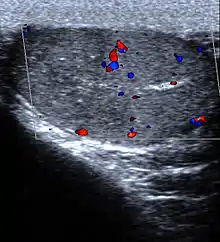

الموجات فوق الصوتية والتي يمكنها الكشف عن تشوهات مثل سرطان الخصية. في حالة انفتال الخصية، يكشف الفحص بالموجات فوق الصوتية الدوبلر الملون انخفاض أو غياب تدفق الدم إلى الخصية.